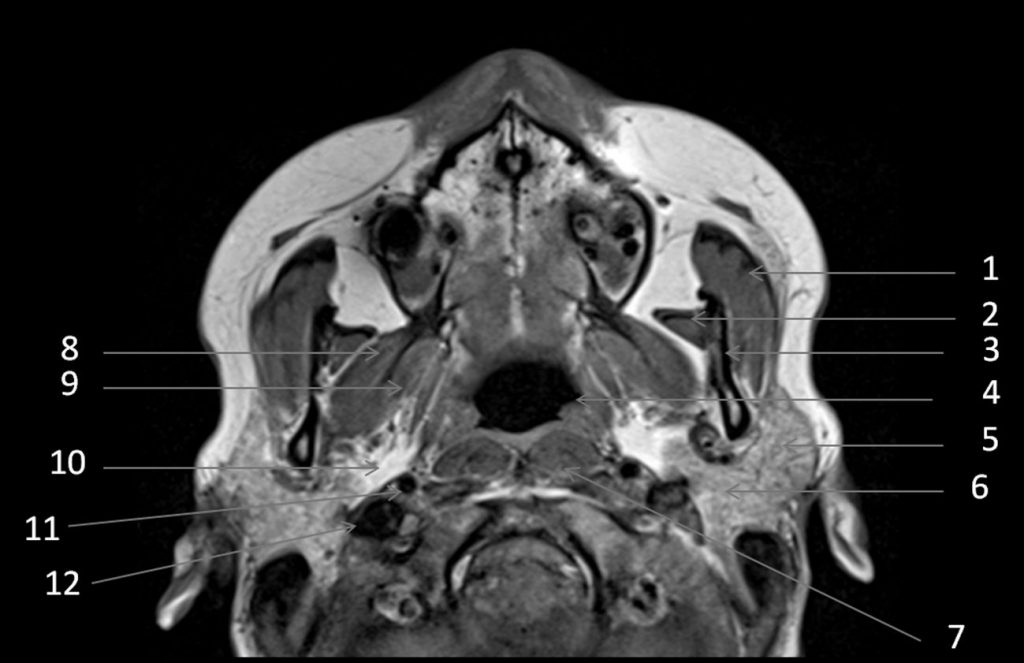

Fig. 62.10 Parotide : IRM, séquence en pondération T1, coupe axiale.

1. Muscle masséter. 2. Muscle temporal. 3. Branche mandibulaire. 4. Nasopharynx. 5. Parotide : lobe superficiel. 6. Parotide : lobe profond. 7. Muscle long de la tête. 8. Muscle ptérygoïdien latéral. 9. Muscle ptérygoïdien médial. 10. Espace graisseux parapharyngé. 11. Artère carotide interne. 12. Veine jugulaire interne.

Source : CERF, CNEBMN, 2022.